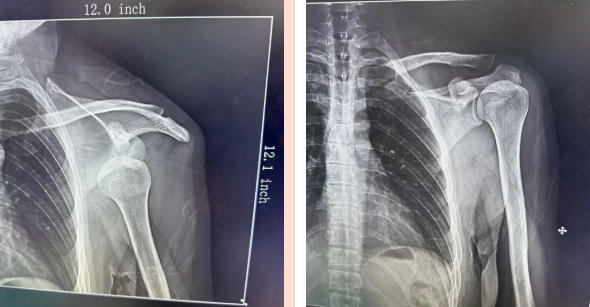

急诊科医生杨新福立即安抚患者,缓解其紧张情绪,询问健身动作并评估病情。X片显示:患者左肩关节脱位,杨新福凭借多年娴熟的复位技巧,仅用时不到2分钟,即成功完成复位。随着一声轻响,马先生紧锁的眉头瞬间舒展,左肩恢复了正常活动功能。